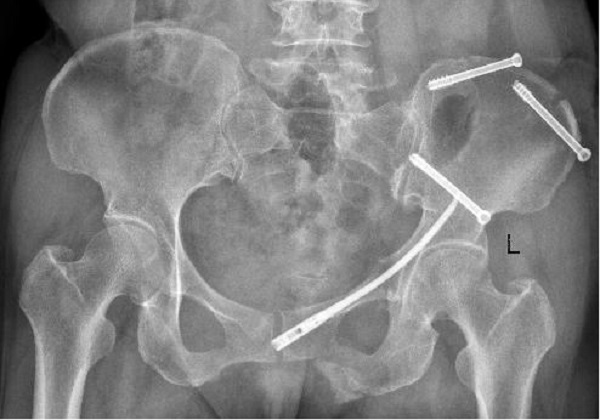

术前X线: